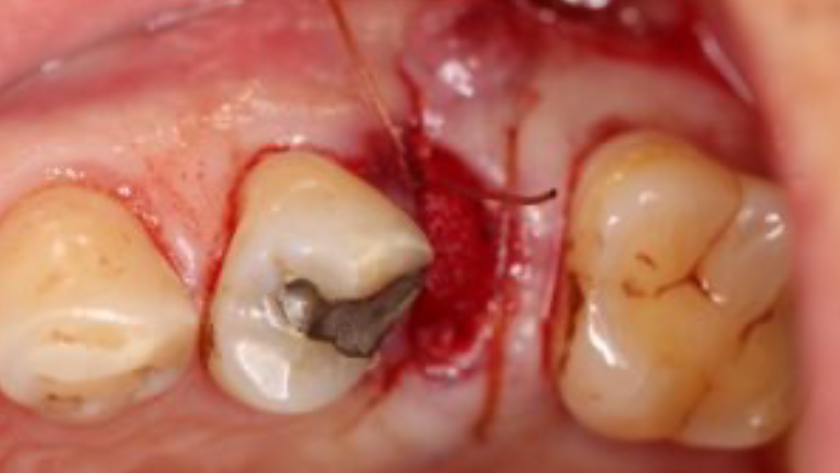

CLINICAL CASE

THE SITUATION

Tooth 13* required extraction in a 54-year-old male patient. The buccal bone was absent. Goal was to restore the site with an implant.